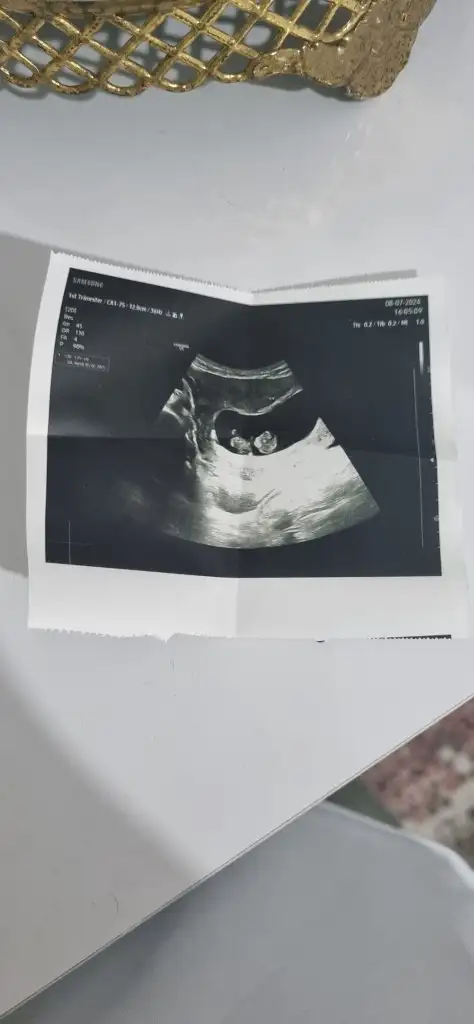

Bende çok merak ettim bak şimdi 3 gebeliğin bu 2 ohlum var bakalım bu ne olacak hayırlısıyla 10 haftalik fotoğrafı karından ultrason

Eklentiler

• 1000030880.webp

1000030880.webp

15,3 KB · Görüntüleme: 65